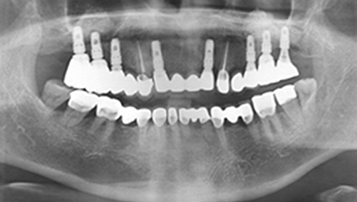

W Dental Clinic Before & After

치료 전후사진

Before

After

뼈이식